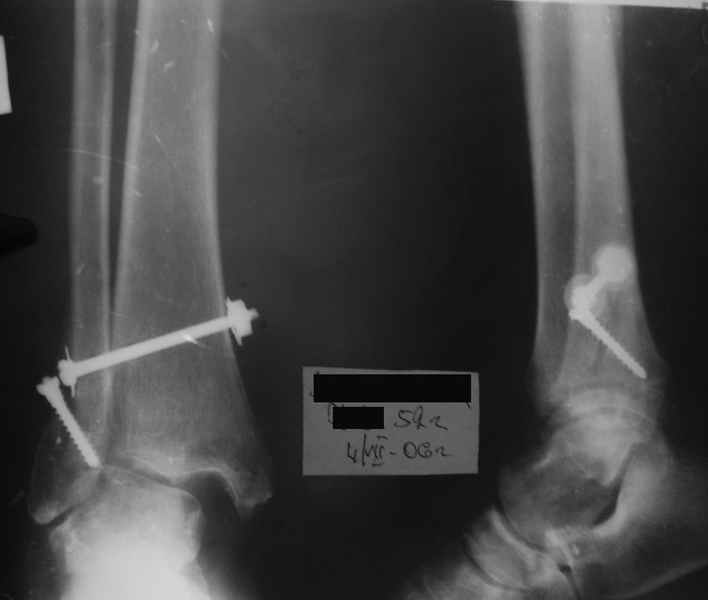

Застарелый подвывих стопы |

Поступает пациентка 52 лет.

Из анамнеза: травма в марте 2006 г., тогда же оперирована в районе, остеосинтез неадекватный.

Что лучше в данном случае предпринять?